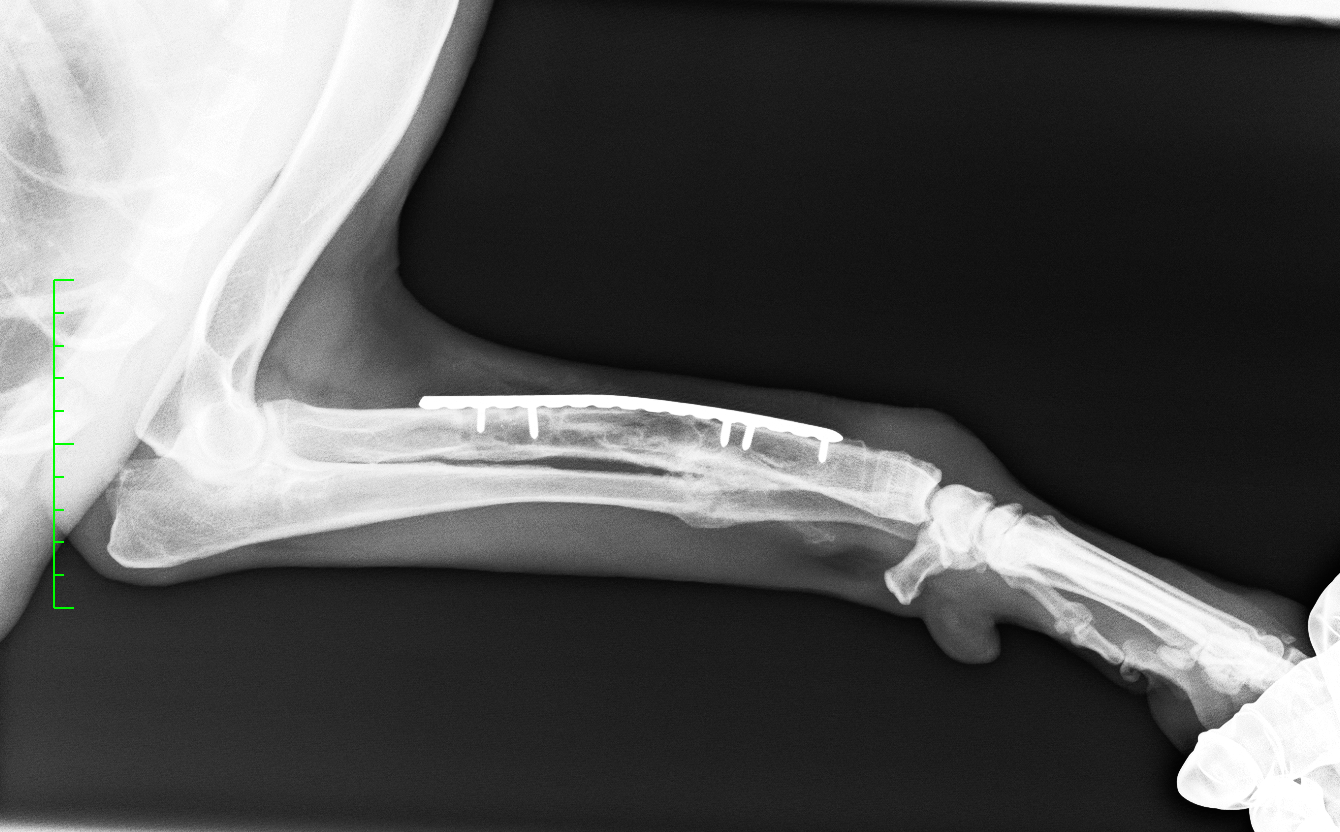

左前肢挙上し、軟部組織の腫脹が認められました。レントゲン、CT検査より橈骨・尺骨の粉砕骨折が認められました

診断と治療

左橈骨・尺骨の粉砕、解放骨折と診断し、橈骨にはLCPのダブルプレート、尺骨には髄内ピンによる治療を行いました

before

after